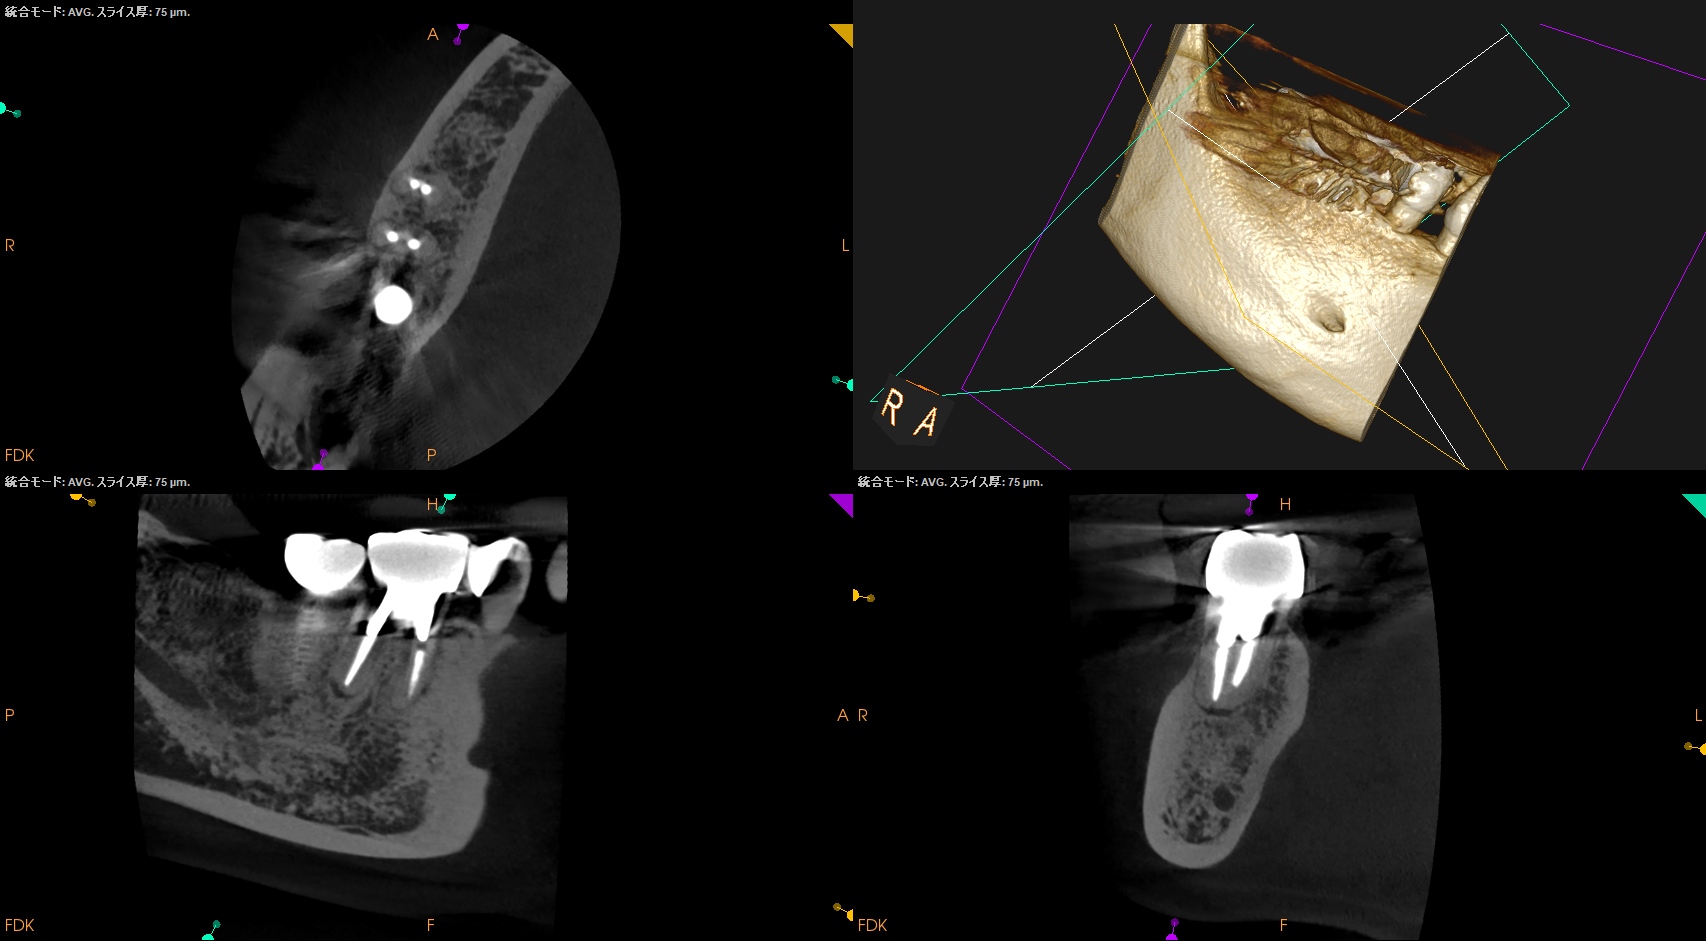

CBCT(2025.10.27)

MB

ML

DB

DL

MのApexに到達するにはCEJよりも12.5mm下方の歯槽骨を2mm削合(Osteotomy)しなければならない。

Apexを見つけたら3mm切断するがこの時の頬舌的な幅径が6.3mmだ。

またDはApexに到達するには、CEJよりも13mm下方の歯槽骨を3mm削合する必要がある。